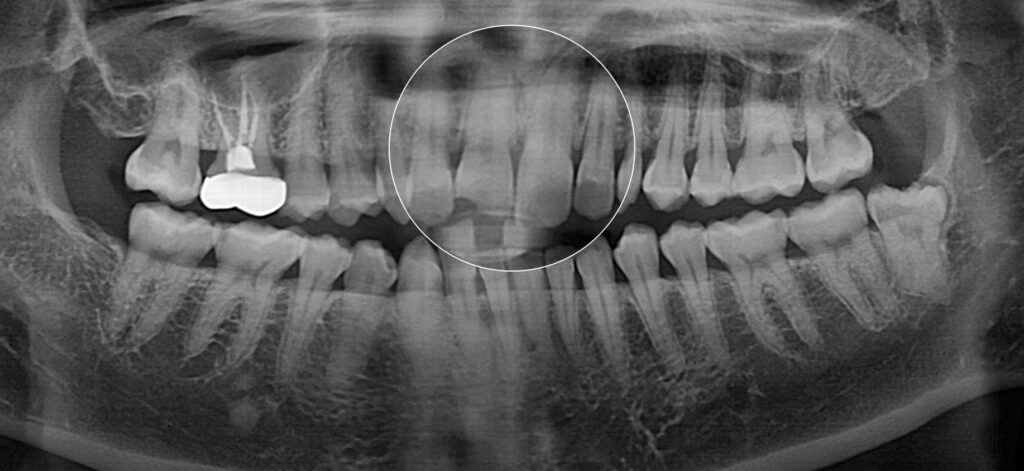

엑스레이 검사에서는

치근의 손상은 관찰되지 않고

주변 골조직도 정상 소견을

보이고 있습니다.

방사선 사진에서도

특별한 이상 소견은 없으면서